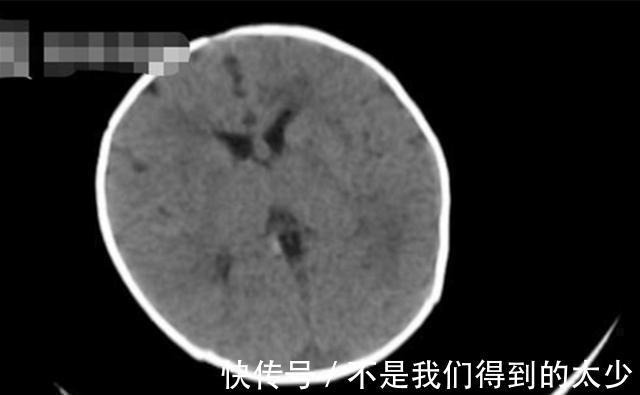

两个孩子送医仔细检查后,居然发现得的全是“脑出血”?这让很多人都难以置信,这种大多只会出现在老人身上的疾病,为什么会在几个月大的孩子身上出现?

原来,宝宝们之所以会出现“脑出血”的情况,主要是因为体内缺乏一种维生素,即“维生素K”。

【 缺乏症|新生儿也会突发脑出血?或因这个“陋习”所致,宝妈们赶紧自查】维生素K是一种有助于血凝的维生素,孩子如果体内缺乏这种维生素,就会有大几率患上“维生素K缺乏症”,这种缺乏症导致的后果就是孩子容易得一系列的“出血性疾病”。

在这其中最危险的也莫过于“脑出血”了。